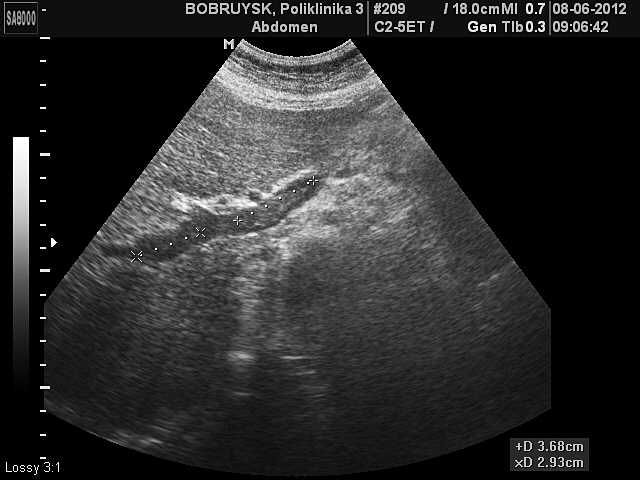

Порто-портальные коллатерали